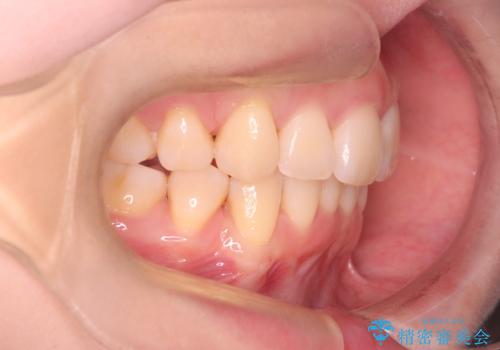

- 前歯が出ていることと、下の歯のがたがたで歯磨きがしにくいことを主訴に来院されました。

マウスピース矯正の希望があり、ワイヤーリカバリの可能性を伝えたうえでインビザライン抜歯矯正を行っています。

治療途中に出産やコロナがあり、2年ほど来院途絶えてしまいましたが、無事治療を終えることができ満足していただきました。

来院が途中途絶えたこともあり、4年ぐらい期間がかかりましたが、インビザラインだけで治療を終えることができました。